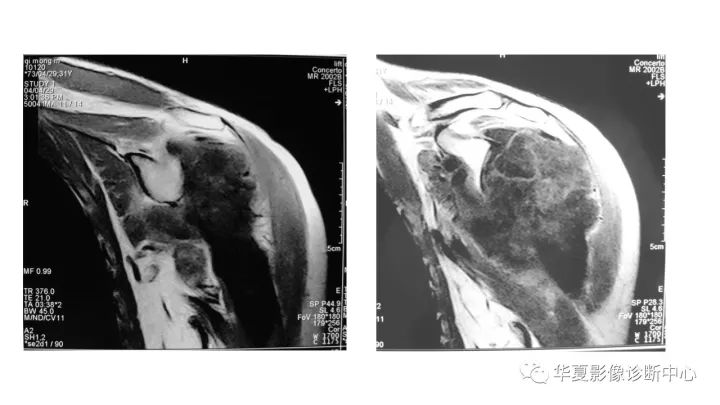

肱骨上段软骨肉瘤1例X线CT及MR影像表现

【病例】肱骨上段软骨肉瘤1例X线CT及MR影像表现